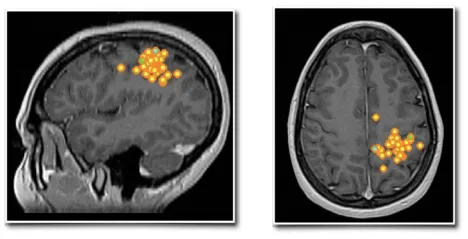

琳娜的MRI检查显示顶叶区域存在小型囊性病变,该病灶被确认为癫痫频繁发作的责任病灶。脑磁图进一步在管理躯体感觉的中央后回区域监测到异常癫痫样放电。下图分别显示矢状位(左)和轴位(右)Rolandic区(中央区)棘波簇(黄色点带橙色轮廓)。

脑磁图(MEG)作为评估过程的重要工具,能够指导术前及术中决策。MEG属于神经生理学技术,通过测量大脑产生的微小磁场实现功能评估。临床实践中常与磁共振成像(MRI)结合使用,创建磁源成像(MSI),将记录到的脑部活动映射至患者三维解剖结构。该技术作为功能性神经影像学方法,特别适用于难治性癫痫的术前评估及术中导航。